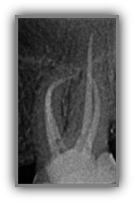

Wurzelkanalbehandlung / Endodontie

Große Defekte, die durch Karies, Stürze oder schwere Parodontitis verursacht werden, können den Zahnnerv schwer schädigen und somit die Erhaltungswürdigkeit des Zahns gefährden. Oft werden solche Zähne einfach entfernt und Patient*innen leiden unter Zahnverlust – wir wollen Zähne erhalten und nicht ersetzen. Die Wurzelkanalbehandlung ist eine zahnerhaltende Behandlungsalternative zum Ziehen des betroffenen Zahns. Im Bereich der konservierenden Zahnheilkunde ist die Wurzelkanalbehandlung eine vielversprechende Methode, einen geschädigten Zahn zu erhalten und so Zahnverlust möglichst zu vermeiden.